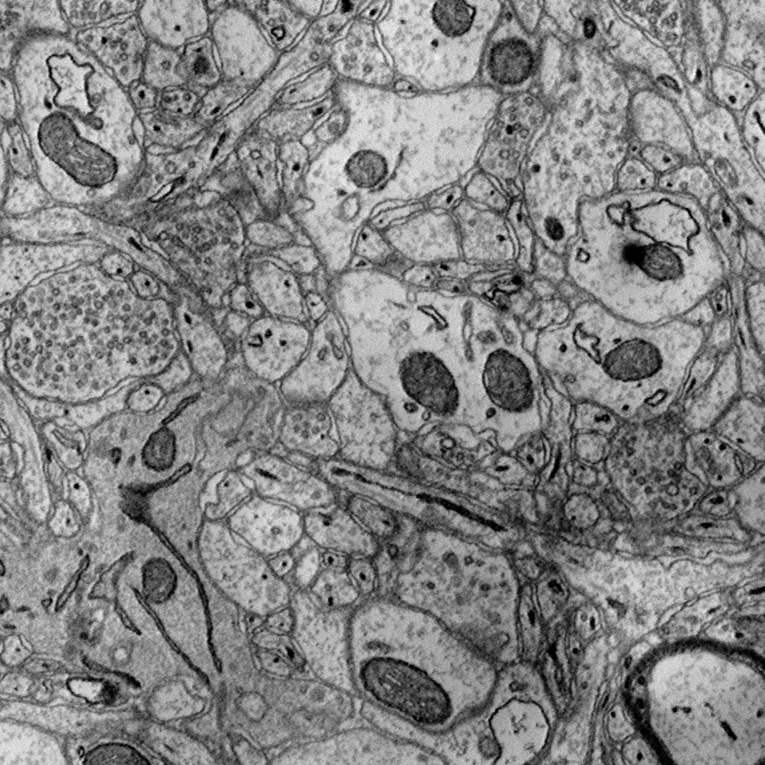

3 Datasets

To analyze the effect of saliency asymmetry in 2D+ representations, experiments were conducted using three datasets: SNEMI, Lucchi, and PA66. Each dataset is composed of grayscale images, which were structured into three-channel representations by stacking temporally or spatially adjacent slices, following a 2D+ approach. Through this setup, spatial continuity was enabled to be captured by the models, while the distribution of saliency across channels was investigated. Figure 2 presents a raw image and its corresponding mask for each dataset.

Refer to caption

(a) SNEMI raw

(b) Lucchi raw

(c) PA66 raw

(d) SNEMI mask

(e) Lucchi mask

(f) PA66 mask

Figure 2: Example images from the three different datasets used in the study. The top row contains raw input images, while the bottom row shows their corresponding segmentation masks.

3.1 SNEMI dataset

The SNEMI dataset contains high-resolution serial-section electron microscopy images of brain tissue, commonly used for neural circuit reconstruction. The grayscale slices depict intricate neural structures such as membranes and synapses, with detailed ground truth annotations available for benchmarking segmentation performance [19, 23, 13, 14].

3.2 Lucchi dataset

The Lucchi dataset focuses on mitochondrial segmentation in brain tissue, presenting anisotropic electron microscopy images with complex cellular environments. The fine-grained grayscale images pose a challenge for feature extraction due to subtle boundaries and variable contrast, making it a valuable test case for assessing biases in pretrained color channel weights.